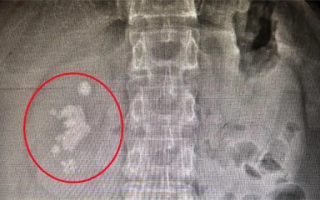

男子查出肾结石未重视拖成大麻烦:发展为铸型结石填满肾脏! 据媒体报道,长沙的向先生十多年前就查出右肾结石,时常感到腰部隐痛,但一直未作处理。直到近期腰部胀痛加剧,影响到日常工作,他才决定就医。没想到检查发现,结石已长成“生姜”形状,几乎填满了整个右肾。医生介... 凹凸曼 2025-10-06 30